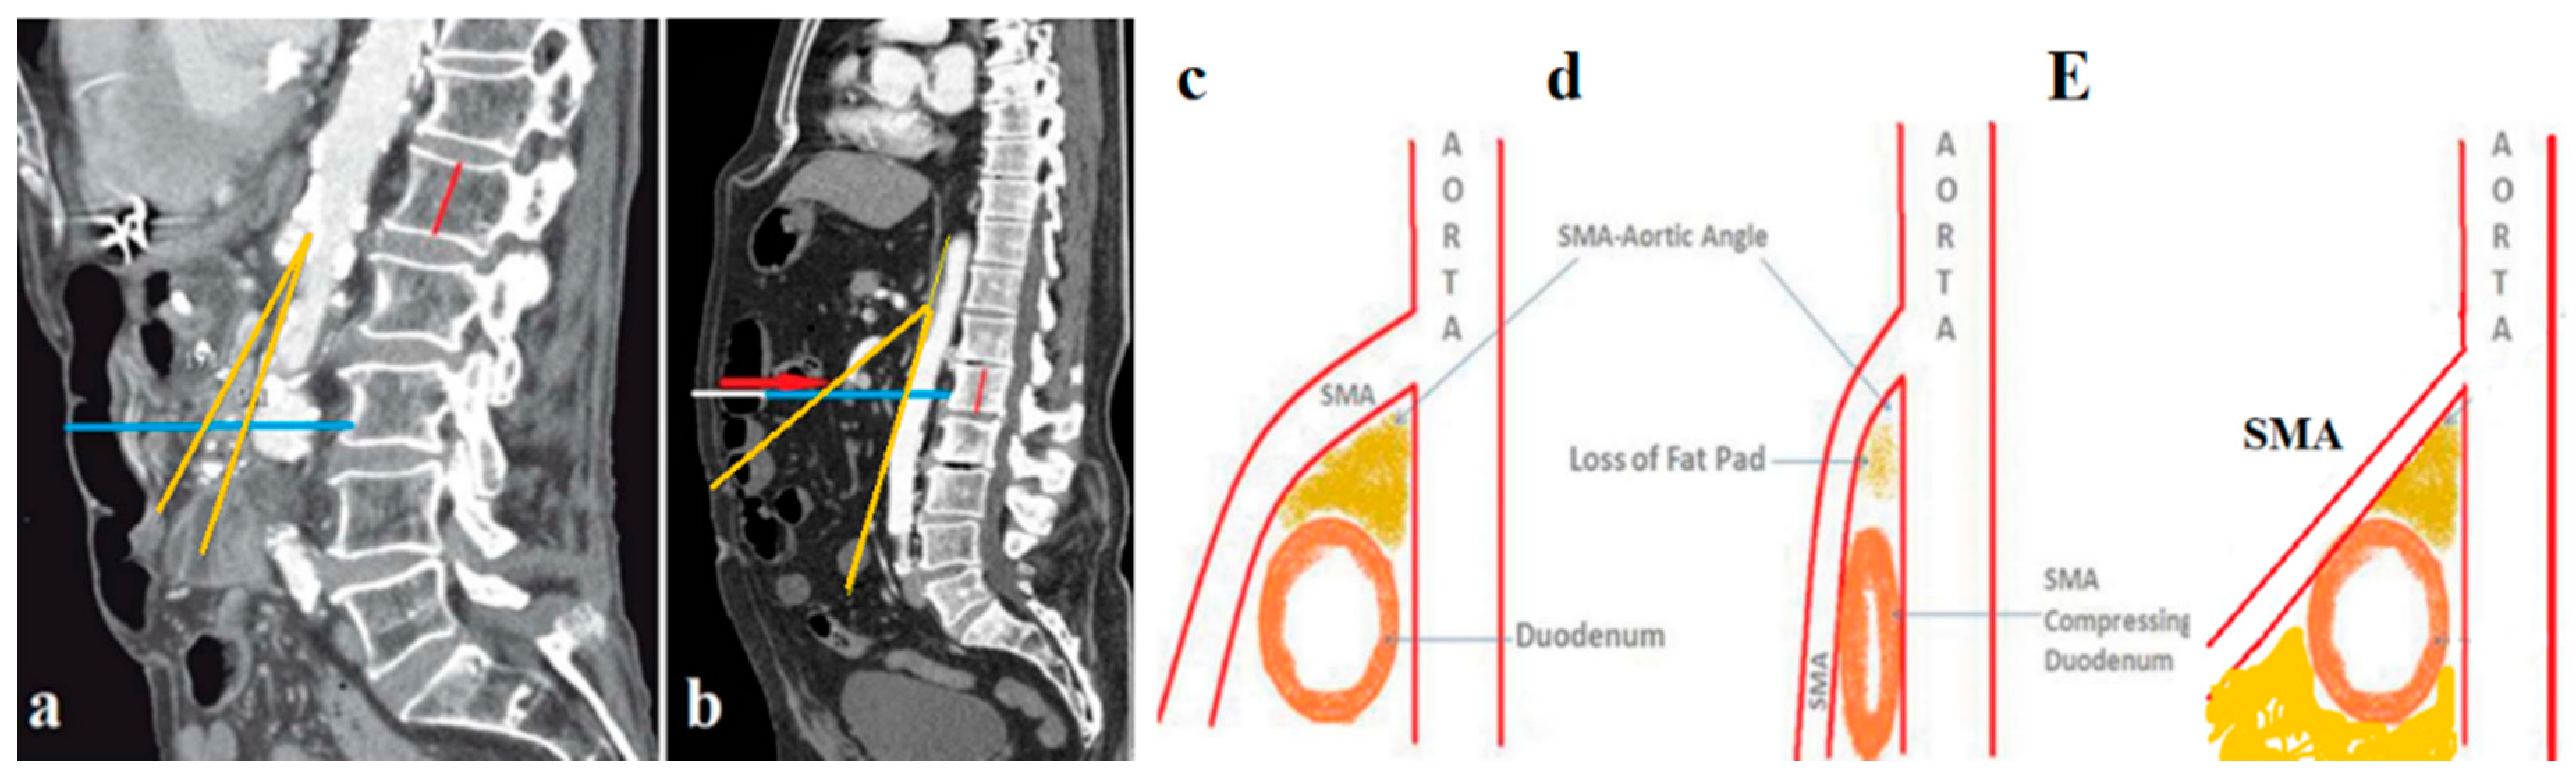

This question is very important, since another, even more improbable hypothesis about the role of adipose tissue in AMA has been proposed to support the vascular hypothesis. The diagram

(Figure 5c,d) shows the principle of this hypothesis. SMAS supposedly arises from the loss of adipose tissue in the AMA, which leads to compression of the duodenum, which passes through this angle. From this follows the principle of SMAS treatment, i.e., hyperalimentation, to increase the volume of adipose tissue and push the SMA anteriorly and thus make room for the duodenum. This hypothesis is rejected by the following evidence. 1) An increase in soft adipose tissue in the AMA cannot push back a tense vessel. 2) An additional volume of adipose tissue competes with the duodenum for space in the AMA, i.e., it can increase its compression. 3) Hyperalimentation can lead to an increase in adipose tissue only with a simultaneous increase in fat throughout the body. This means that for enough fat to appear in the AMA, the patient must gain tens of kilograms. This cannot be done not only in a few days, but also in many months, especially since we are talking about a violation of the patency of the duodenum.

Figure 5a,b,E provides further evidence that “when BMI of a patient decreases, there is a corresponding reduction in SMA angle and distance» [

14,

12].